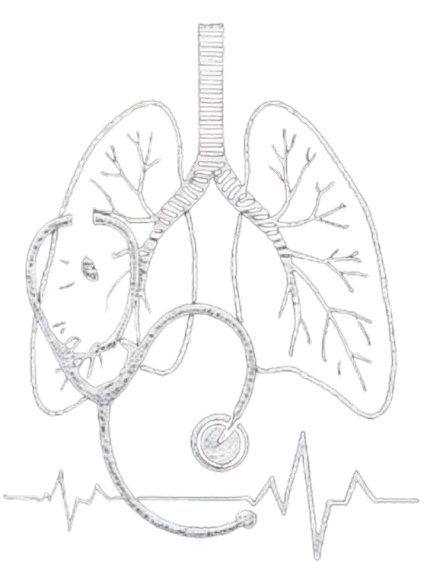

Element Type:File

Logo:IMG_0017-removebg-preview.png